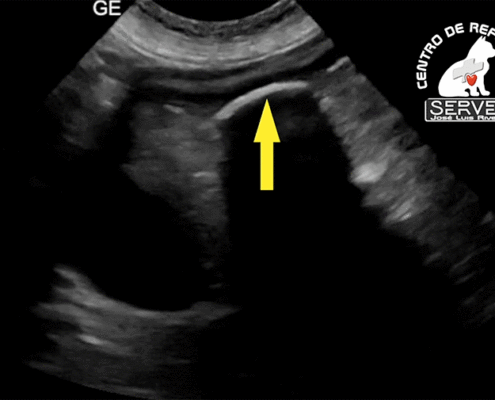

Un equipo de veterinarios y técnicos, coordinados y con medios suficientes para cada caso pueden conseguir sacar a un animal de una situación crítica incluso letal. El laboratorio en pleno funcionamiento, La sala de radiología y tomografía, presentes en el centro agilizan la obtención de información del estado del animal y posibilitan la administración del tratamiento más adecuado